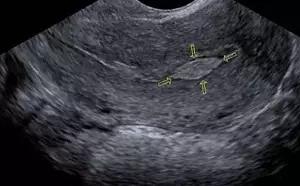

B超所见的内膜息肉(箭头所指)